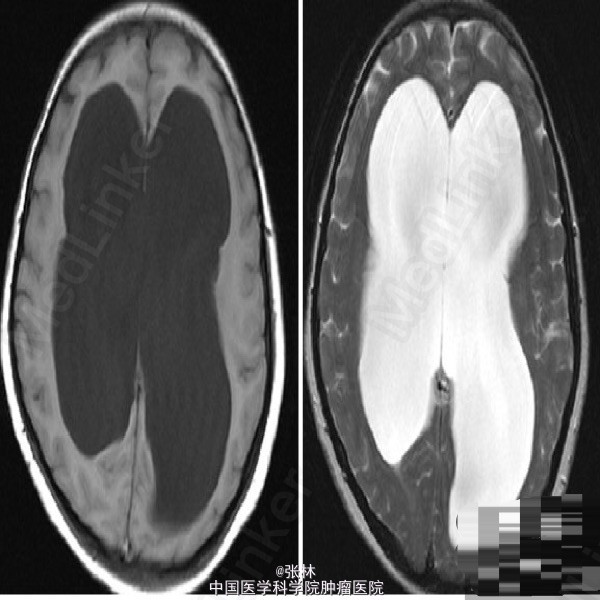

【病史临床】女,48岁,走路不稳十年,伴记忆力下降。【影像表现】 双侧大脑半球对称,全脑室系统明显扩张,脑质明显受压变薄,未见局灶性信号异常。增强扫描未见异常强化。中线结构居中,脑干细小,矢状面示垂体大小形态正常,未见局灶性信号异常。 【诊断】 交通性脑积水 【鉴别诊断】 1、梗阻性脑积水;2、脑萎缩 【讨论】 交通性脑积水是指第四脑室出口以后的正常脑脊液通路受阻或吸收障碍所致的脑积水。常见原因为蛛网膜下腔出血、脑膜炎、外伤、静脉栓塞等。临床症状有头痛、呕吐、复视等颅高压症状。 影像诊断要点:脑室系统普遍扩大,脑沟正常或消失,早期颞角扩大,后期额角扩大,第三脑室,侧脑室体部和第四脑室扩张,脑室旁脑白质可见间质水肿。与脑萎缩鉴别为后者脑室扩大缺乏张力,伴脑沟扩大。与梗阻性脑积水鉴别要点为后者阻塞近侧脑室扩大,远侧脑室正常。当阻塞段位于第四脑室出口时鉴别困难,需要结合多轴面以及增强判断第四脑室与蛛网膜下腔的通畅情况。